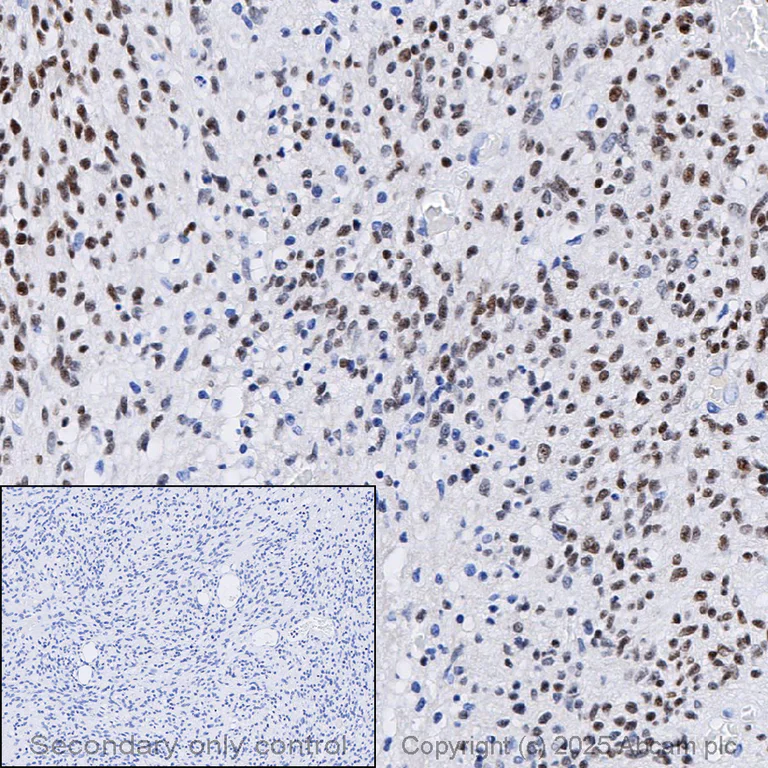

Immunohistochemistry (Formalin/PFA-fixed paraffin-embedded sections) - Anti-FOXG1 antibody [EPR18987] - BSA and Azide free (AB227888)

This data was developed using ab196868 the same antibody clone in a different buffer formulation.

Immunohistochemical analysis of formalin fixed paraffin embedded human glioma labelling FOXG1 with ab196868 at a concentration of 0.5µg/ml. The immunostaining was performed on a Ventana DISCOVERY ULTRA (Roche Tissue Diagnostics) instrument with a OptiView DAB IHC Detection Kit. Heat mediated antigen retrieval was performed with DISCOVERY cell conditioning solution (CC1) 100°C, pH8.5 for 32mins. ab196868 Anti-FOXG1 antibody [EPR18987] was incubated for 16mins at 37°C. Sections were counterstained with Hematoxylin II. Image inset shows absence of staining in secondary antibody only control.

Customers are encouraged to optimise antigen retrieval conditions, antibody concentration, incubation times and temperature for best results in their own IHC assay workflow (automated and manual).